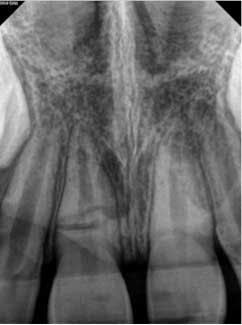

At three months, the clinical testing was equivalent and radiographs showed a fracture still present, but the periodontal ligament (PDL) and lamina dura (LD) were intact and uniform, especially near the fracture line (figure 2). At six months, there was no change in the response to vitality testing and radiographs continued to show no deleterious changes (figure 3).